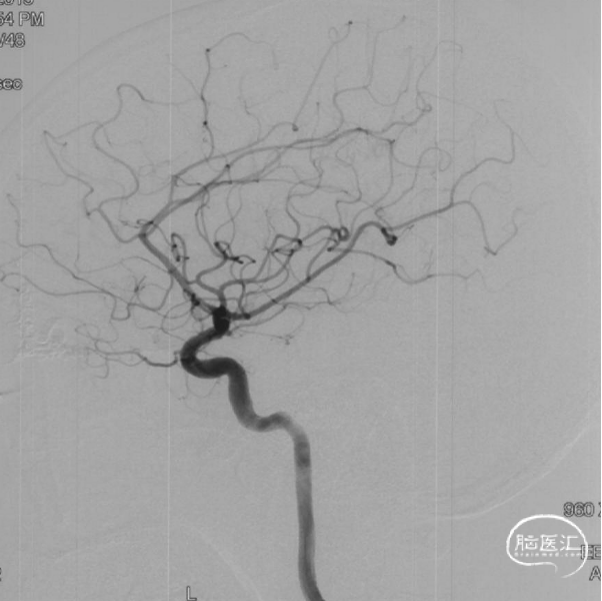

术前造影

双侧颈内动脉正侧位造影见前颅窝底硬脑膜动静脉瘘,双侧筛前动脉、筛后动脉向瘘口供血,通过皮层静脉向上矢状窦引流。

双侧颈外动脉正侧位造影见镰前动脉向瘘口供血。

左侧椎动脉正侧位造影未见明显异常。